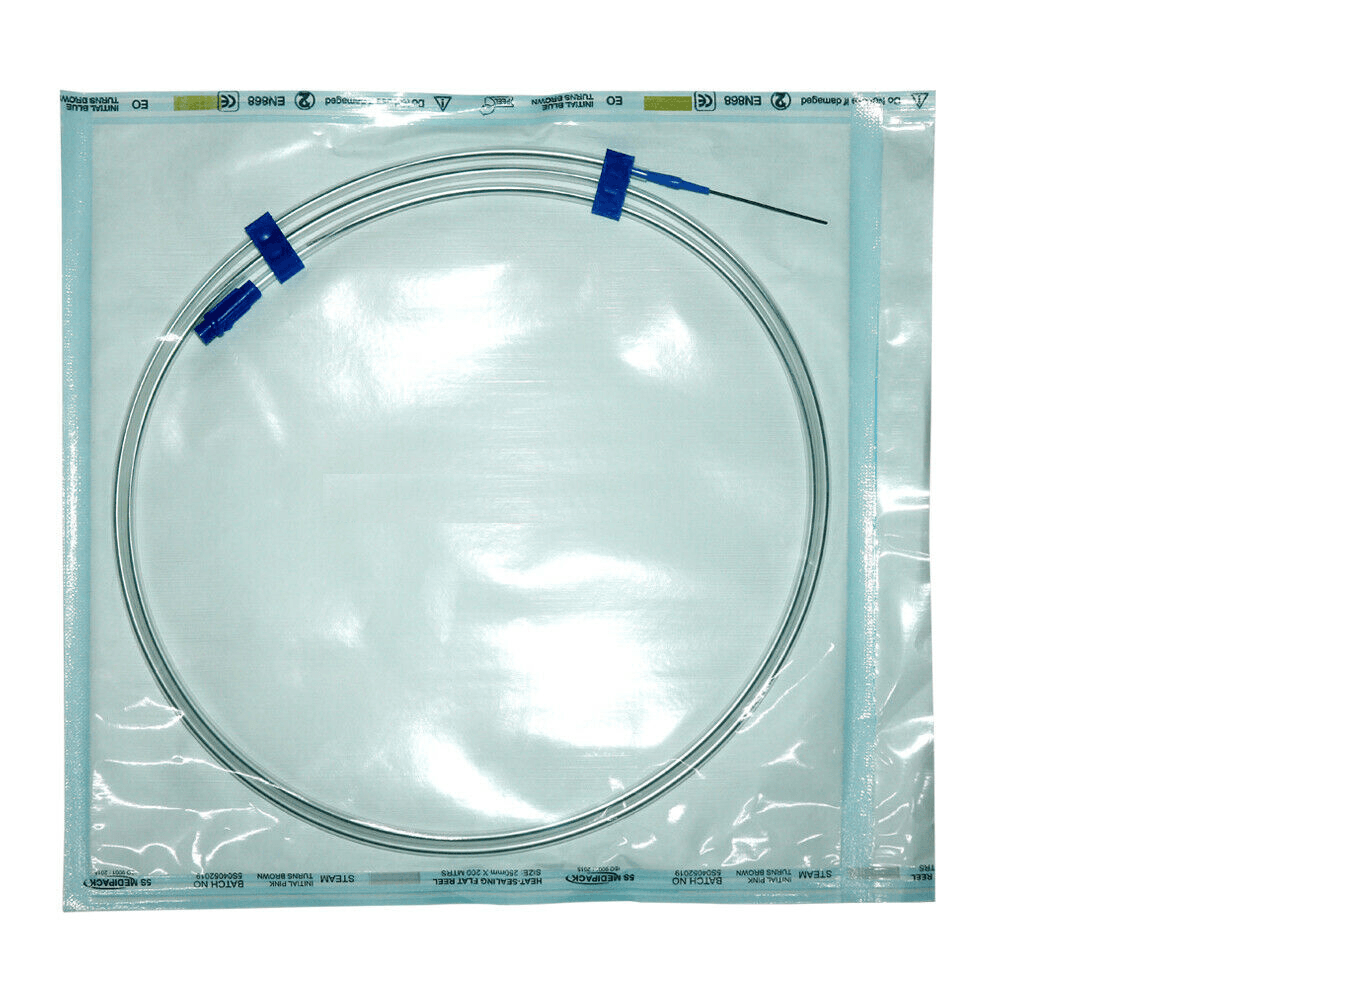

PTFE Guide Wire Set of 10 Urology Size 0.035 Length 150cm Straight

PTFE Guide Wire Set of 10 Urology Size 0.035 Length 150cm Straight

Guide wire with and without PTFE coating

- This wire is made by Galvanized Stainless Steel, and having fixed core. UROMED guide wire has excellent flexibility.

- Better push ability for increased placement control.

- Low of coefficient of friction for smooth advancement.

- Size: 0.035”

- Lengths: 150cm

Images are for illustration only. Company may change item design and packaging from time to time. We will ship latest stock available.